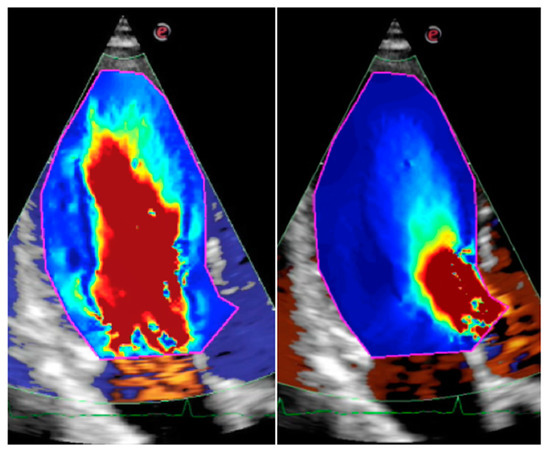

3.2. Cardiac Ultrasound Techniques

- Fiorencis, A.; Pepe, M.; Smarrazzo, V.; Martini, M.; Severino, S.; Pergola, V.; Evangelista, M.; Incarnato, P.; Previtero, M.; Maglione, M.; et al. Noninvasive Evaluation of Intraventricular Flow Dynamics by the HyperDoppler Technique: First Application to Normal Subjects, Athletes, and Patients with Heart Failure. J. Clin. Med. 2022, 11, 2216. [Google Scholar] [CrossRef] [PubMed]